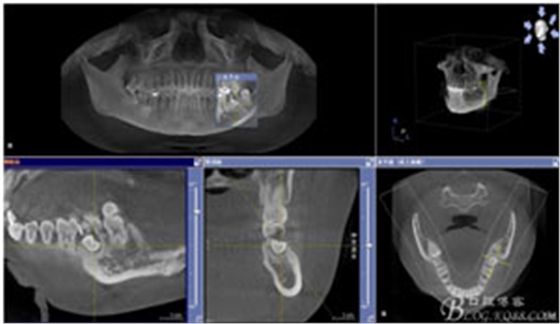

患者、申xx、女、40歲,主訴:左側(cè)下頜后牙牙齦紅腫不適數(shù)月。??茩z查:37合面有一開(kāi)髓孔。髓腔內(nèi)有一暫封小棉球,探針?biāo)枨坏撞砍鲅?,疑為在外院治療?dǎo)致底穿。x線片檢查:37頰側(cè)齦下有一枚多生牙,多生牙壓迫頰側(cè)牙根及牙體組織大量吸收。

圖1.術(shù)前的CBCT檢查:37頰側(cè)部分牙根被完全壓迫吸收。